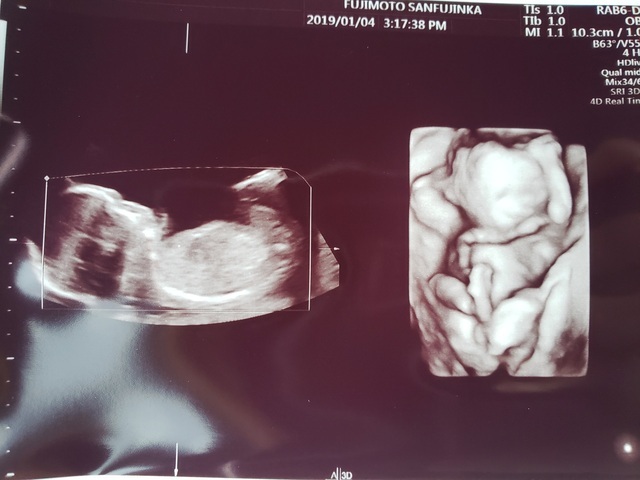

18週6日(18w6d・女の子)|loncyi さん(38歳)

エコー写真撮影時のエピソード:

写真なのが、伝わりにくいのが残念ですが、ムービーで撮った時には、手を動かして、踊っているんです。 母が踊るのが好きだからか、子どももお腹の中で踊ってるのかな?

でも、実際に生まれてきた娘は、踊りと歌が大好きな女の子。 お腹の中にいるときから、大好きだったのね!